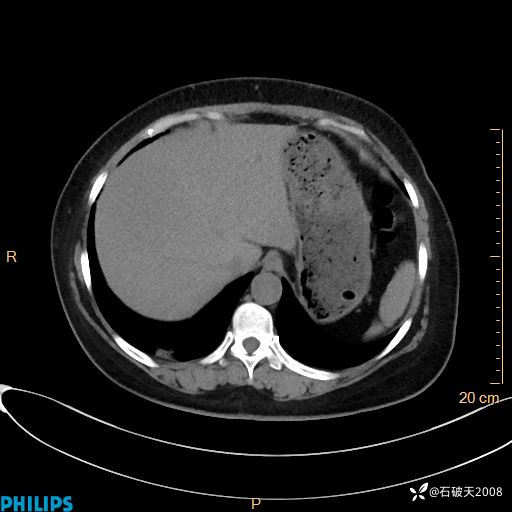

纵隔窗